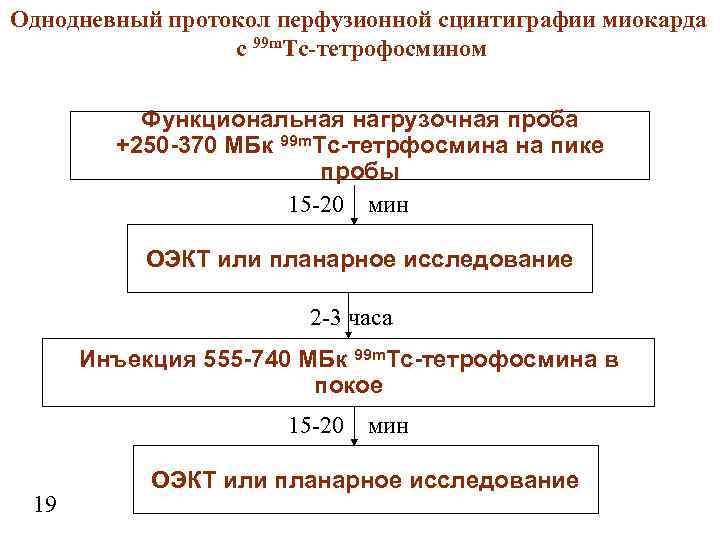

Однодневный протокол перфузионной сцинтиграфии миокарда с 99 m. Тc-тетрофосмином Функциональная нагрузочная проба +250 -370 МБк 99 m. Тc-тетрфосмина на пике пробы 15 -20 мин ОЭКТ или планарное исследование 2 -3 часа Инъекция 555 -740 МБк 99 m. Тc-тетрофосмина в покое 15 -20 мин 19 ОЭКТ или планарное исследование

Однодневный протокол перфузионной сцинтиграфии миокарда с 99 m. Тc-тетрофосмином Функциональная нагрузочная проба +250 -370 МБк 99 m. Тc-тетрфосмина на пике пробы 15 -20 мин ОЭКТ или планарное исследование 2 -3 часа Инъекция 555 -740 МБк 99 m. Тc-тетрофосмина в покое 15 -20 мин 19 ОЭКТ или планарное исследование